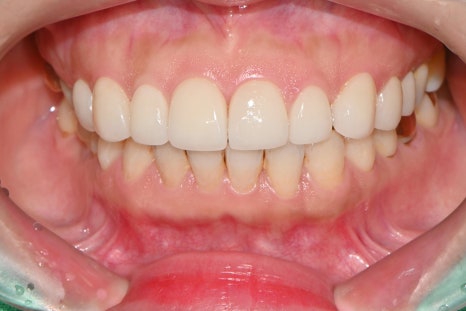

치료 후 결과

이번 사례는 치아 삭제 없이 진행된 무삭제 라미네이트로, 단 2회 내원만으로 모든 과정이 완료되었습니다.

• 과하게 두껍지 않은 슬림한 형태 유지

• 환자분이 원했던 가장 밝고 깨끗한 A1 색상 구현

• 벌어진 틈을 완벽히 메워 균형 잡힌 스마일 라인 완성

환자분께서는 "치아 삭제 없이 원하던 모양과 색상이 그대로 나왔다"며 매우 높은 만족감을 표현해 주셨습니다.